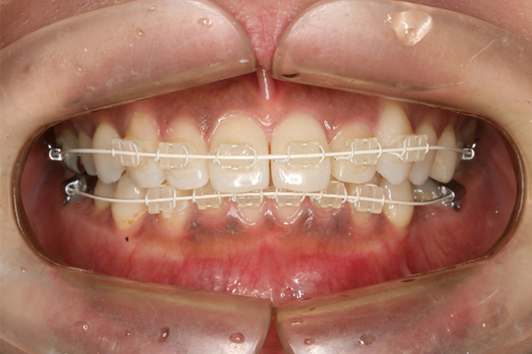

日本人の歯の色に合わせたブラケットとホワイトワイヤー

装置が見えない裏側矯正と矯正用インプラント